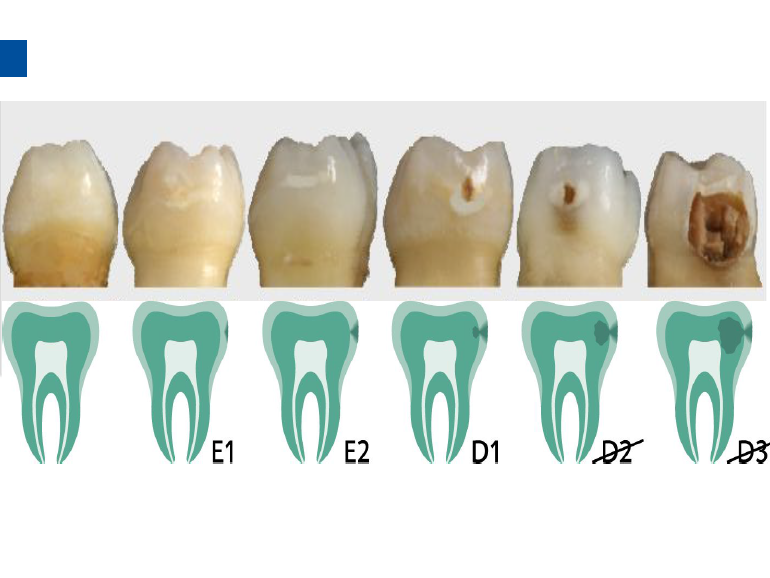

微创牙科治疗是一种全新的龋病治疗理念,着眼于疾病的早发现、早诊断、早治疗。树脂渗透治疗是介于再矿化治疗和充填治疗之间的一种创新的治疗手段,通过微量的去除牙体组织,达到加固脱矿釉质、阻止进一步脱矿的目的。

lcon渗透基于封闭釉质龋空隙的一种特殊树脂的渗透,封闭釉质龋小孔,从而阻断致龋酸传播途径,阻止龋病进一步发展。这种材料操作方法简单,对牙体组织损伤轻微,不用通过麻醉和磨切牙体来达到加固脱矿釉质,同时可以改变釉质龋表面的白色或棕色改变,达到美观修复效果,是对龋病微创治疗的突破。